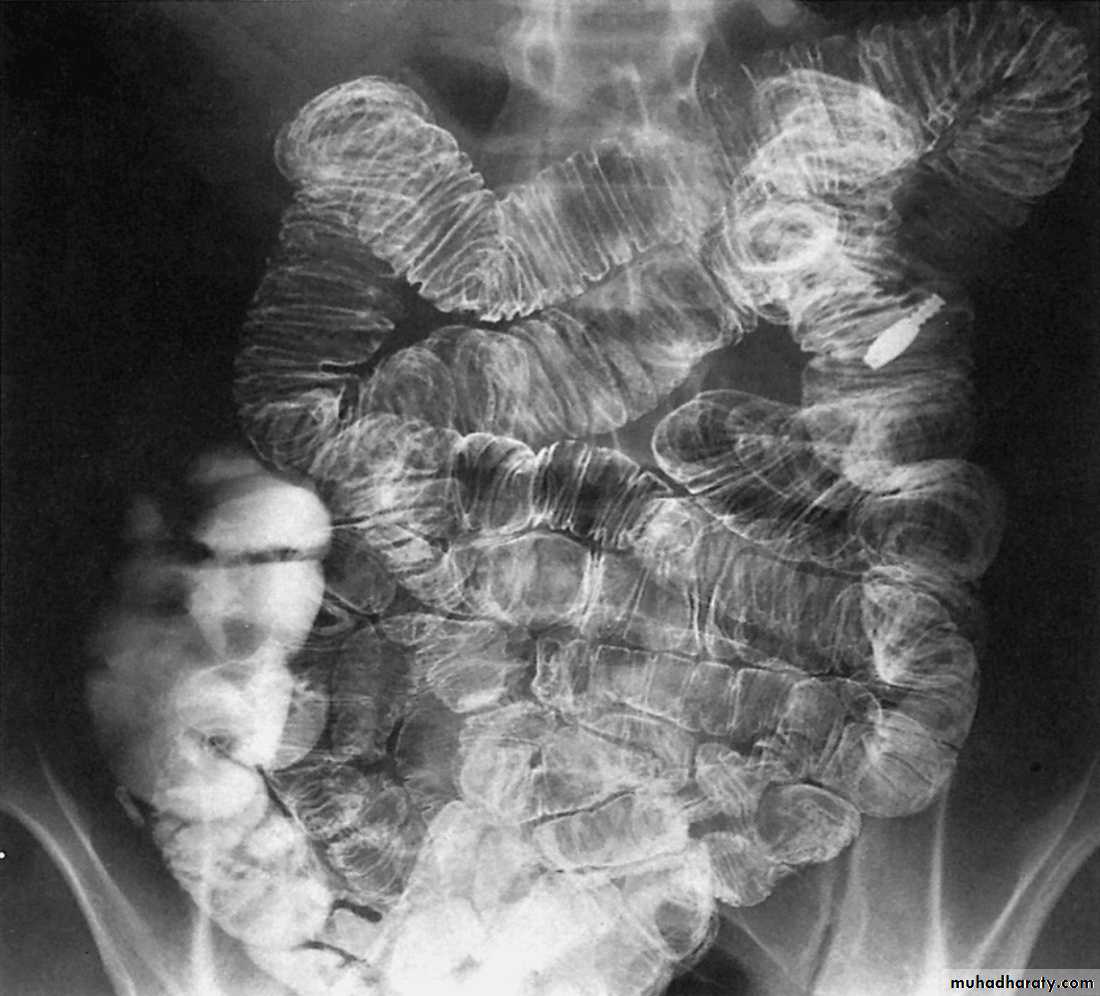

The standard contrast examination is barium follow-through (that involves drinking 200-300 ml of barium then taking films at regular intervals until the barium reaches the colon). It may take 2-3 hoursNormal barium follow-through

The barium forms a continuous column defining the diameter of bowel (< 25 mm). Transverse mucosal folds appear as lucent filling defects of about 2-3 mm in width. When the SB is contracted, their appearance is described as feathery. The folds are largest & numerous in jejunum & tend to disappear in the lower parts of ileum.enteroclysis

Multiple dilated small bowel loops are present. The valvulae conniventes

are thin and straight and closely stacked together.